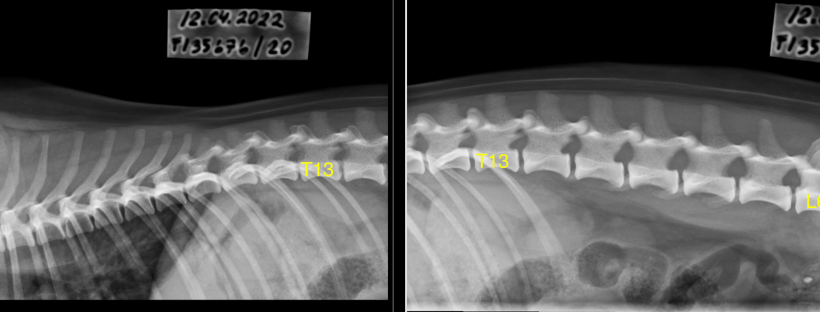

Noniin, nyt on Sallinkin luustokuvien tulokset selvillä! Lonkat palautuivat Suomen Kennelliitosta C/C ja kyynärät 0/0. Lonkkamaljoissa mataluutta, minkä vuoksi C:t, mutta niilläpä pikkuisen volpinon pitäisi pärjätä erinomaisesti koko elämänsä ilman ongelmia. Saa siis jatkaa normaalia reipasta koiran elämää ilman, että lonkkien kunnosta pitäisi juurikaan olla huolissaan. Hyvässä lihaskunnossa vaan pitää koiran. Kyynärät terveet, ei muutoksia. … Jatka artikkeliin Mietteitä Sallin luustokuvista